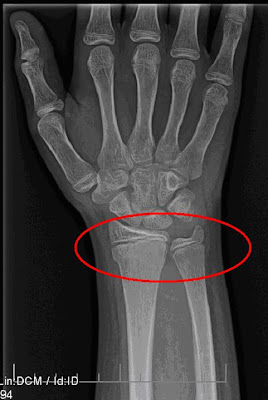

That my friends is a picture of a broken wrist. Does anyone want to start guessing whose wrist? Go ahead, guess......

It's Moira's!!!!!! Yes, MOIRA'S!!!!! We have made a few possible conclusions to all of this. Moira has either missed visiting ER's, she was hoping to visit all the different hospitals in the area to get a souviner from each gift shop, OR she is trying to match her Build-A-Bear (She got that while she was in the hosptial for her appendectomy. The bear has it's arm in a sling, a cast on his leg and comes a crutch.). Either way, we think she needs to stop visiting hospitals :-)

So what happened? Well were hanging out with our church's small group at a local park. The kids and some of the adults decided to play a game, similar to Marco Polo, just out of water. One of the adults jumped back, trying to keep out of the reach of the person who was "It", and knocked Moira over, who happened to be standing behind them. She fell back and tried to break her fall with her left hand. Which resulted in the above break. I didn't see the actual fall, but did see Jeremiah and the other person 'tending' to Moira who was lying on the ground. I thought, "oh, no, Moira got hurt, poor thing." Then I saw that she had her left hand on her tummy, and my first thought was, "OH, NO! Something happened to her abdomen!" I quickly tried to think if we had somehow not given her enough time to heal.....Then I heard Moira crying out, "OWWWW, my wrist, my wrist!!!" So my next thought was, "Oh, Lord, why her?" We examined, ever so tenderly, her wrist, and while doing so (all of a minute or two) her wrist started to swell right before our eyes. But I knew with the way she was crying that it was either broken, or popped out of joint. So we loaded everyone in the van and took her to the closest ER. Jeremiah stayed with her and I took the rest of the crew home. It's only a 25 minute drive, but we did make a 15 minute stop at Walmart for a snack and to nurse a very fussy baby. Not 30 seconds from walking in the door Jeremiah was calling to say it was x-rayed and they were waiting for it to be put in a splint. About 25 minutes later he called to say come get them!! Wow! So I headed back out to pick them up. Thankfully by that time the Advil we had given to her just moments after the accident, had kicked in. So she was a happy camper.